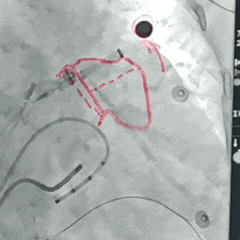

封堵器展开后肝位造影,封堵器完全封堵,无残余分流

回弹明显,封堵器稳定锚定在心耳内部

该病例为鸡翅型左心耳,心耳上叶解剖特征呈梯形状,内窄外宽,利于封堵器倒刺稳定锚定心耳内,MemoLefort封堵器通过封堵器贴壁成角倒刺钩挂住远端梳状肌可使封堵器稳定在心耳内,合适的封堵器选择使封堵器肩部骨架提供二次稳定,形成稳定封堵,术中LAFDQ-29封堵器牵拉稳定,压缩比合适,稳定覆盖心耳内部。